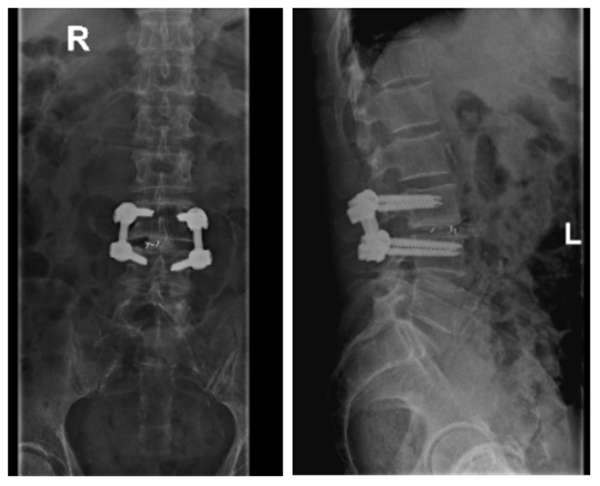

与廖老师及其家属沟通并获得同意后,张勇华主任与省人民医院帮扶专家黄勇兄主任共同为廖老师进行了手术治疗,行椎管扩大减压、椎间融合、椎弓根钉内固定术,术后患者安返病房。住院康复期间,廖老师肢体活动及麻痛情况已比以前明显好转,能顺畅行走,两周后顺利出院。